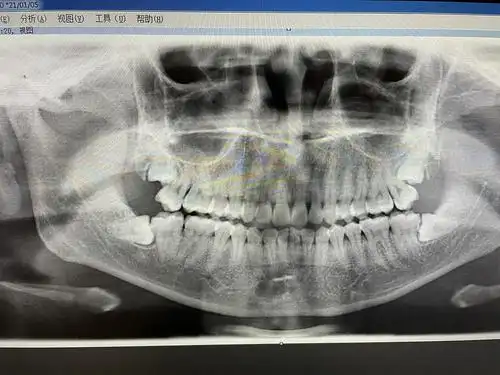

今天去拍了免费的牙片然后发现了很值钱的智齿

牙片鉴赏友友们看看我的智齿急不急着拔呀

即将拔智齿求看牙片

俺的牙片来啦 友友们看看俺的智齿怎么样

智齿发炎拍了牙片感觉人生从此转折з

分享一下我的牙片 以及上面的智齿需要拔吗